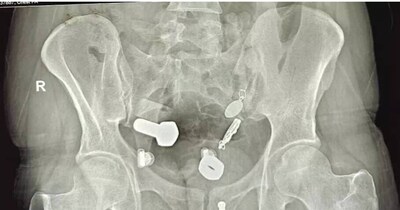

केरल की महिला के शरीर में 2021 की सर्जरी के पांच साल बाद एक्स-रे में सर्जिकल उपकरण मिला.

•अलप्पुझा मेडिकल कॉलेज में 2021 की सर्जरी के लगभग पांच साल बाद उषा जोसेफ के पेट में एक सर्जिकल उपकरण, आर्टरी फोरसेप्स, मिला.

•जोसेफ को सर्जरी के बाद लगातार पेट दर्द हो रहा था; किडनी स्टोन के संदेह में कराए गए एक्स-रे में विदेशी वस्तु का पता चला.